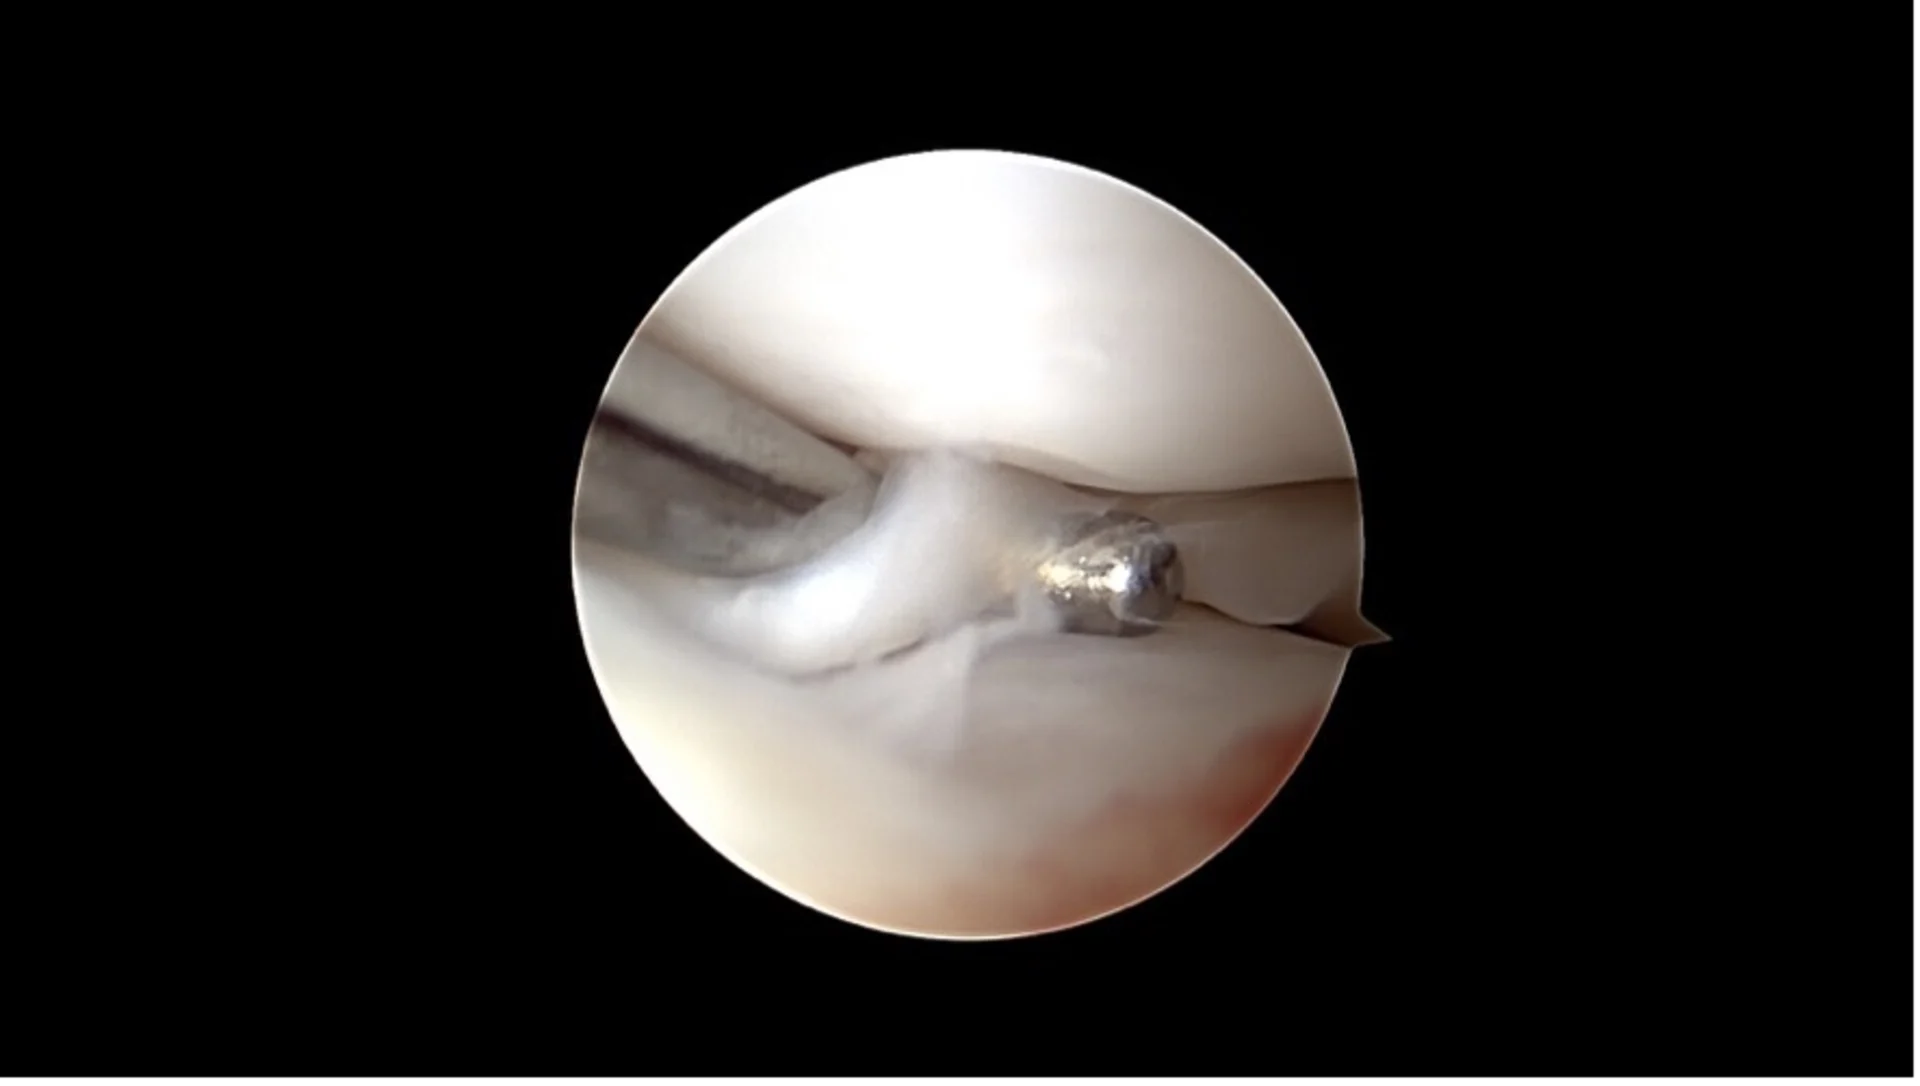

Rupture méniscale en anse de panier

Arthroscopie

Une caméra miniaturisée permet de visualiser directement l’intérieur de l’articulation par de petites incisions cutanées. Les lésions du ligament croisé et les dommages associés comme les déchirures du ménisque peuvent être diagnostiqués et souvent traités immédiatement.